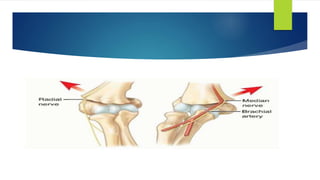

If neurovascular bundle impaired

 Sensory examination

 Radial

 Median

 Ulnar

 Motor

 AIN